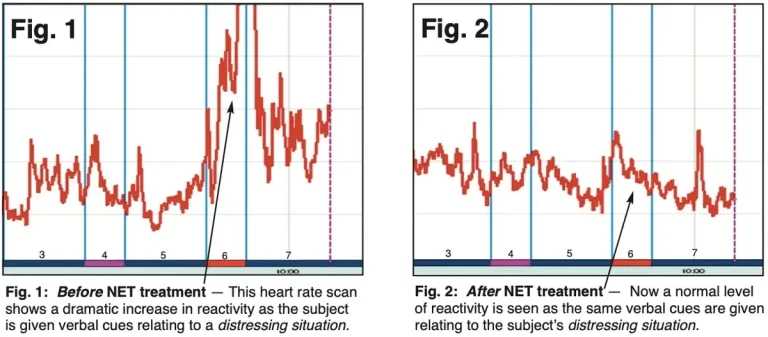

According to a study published in October 2017 titled “Changes in Cerebellar Functional Connectivity and Autonomic Regulation”, researchers found that:

“For the first time, a treatment for traumatic stress was shown to alter cerebellar connectivity with limbic structures and the brainstem. These changes were linked to reduced symptoms and decreased autonomic reactivity (such as heart rate) in response to traumatic stimuli.”